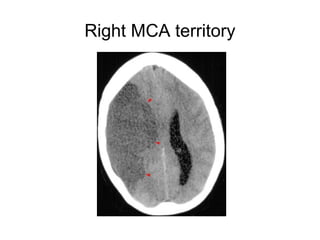

Right MCA territory

CT SIGNS

1.Hypoattenuating brain tissue

• The diagnosis is infarction, because of the

location (vascular territory of the middle

cerebral artery (MCA) and because of the

involvement of gray and white matter,

which is also very typical for infarction.

2.Obscuration of the lentiform

nucleus

• Obscuration of the lentiform nucleus, also

called blurred basal ganglia, is an

important sign of infarction.

It is seen in middle cerebral artery

infarction and is one of the earliest and

most frequently seen signs.

The basal ganglia are almost always